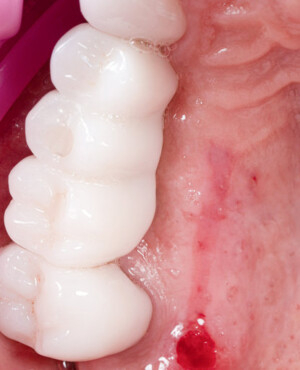

Aditia gingivală este o procedură chirurgicală ce corectează diverse probleme estetice și funcționale, cum ar fi recesiunea gingivală. În implantologia modernă, aditia de țesut moale este utilizată aproape în fiecare intervenție de inserție a implantului dentar pentru a asigura un aspect estetic natural și o bună integrare a implantului în cavitatea bucală.

Adiția osoasă are un rol crucial pentru poziționarea corectă și stabilă a implanturilor dentare. Clinica stomatologică Dr. Grossu din Chișinău promovează o abordare chirurgicală estetică și predictibilă, adaptată fiecărui caz în parte.

Medicii noștri au o vastă experiență atât în chirurgia estetică, cât și în protezarea cu un grad înalt de naturalitate, ceea ce ne permite să gestionăm cu succes și cele mai complexe cazuri.